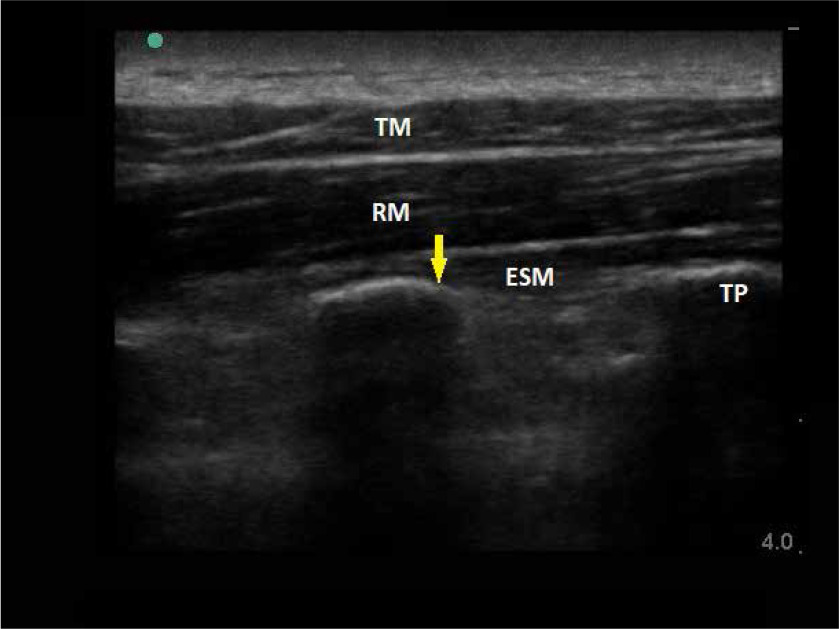

FIGURE 8

Sonoanatomy of the erector spinae plane block. TM – tra- pezius muscle, rhomboid muscle, TP – transverse process. Yellow arrow indicates site of LA deposition

ESP blockade is an ultrasound-guided compartment block used as part of multimodal analgesia, mainly after abdominal and thoracic surgery. the first description of the blockade was presented in 2016. Forero et al. presented the effect of ESP blockade in the interventional treatment of neuropathic pain after thoracic surgery [18]. the following years and scientific reports influenced the broad development of indications for the blockade and its implementation in various clinical situations. ESP blockade consists of the deposition of lAs in the fascial compartment between the erector muscle of the spine and the trans-verse process of the thoracic vertebrae. in the case of breast surgery, the t3–t5 level is recommended for LA injections. the administration of LAs at the appropriate level and in the relevant fasciomuscular compartment guarantees broad transmission of the drug in the cephalic and caudal directions. Figure 7 demonstrates the anatomy of the thoracic paraspinal region. in addition to distribution in the sagittal plane, the resting tension of the tissues (muscles and fascia) also causes the penetration of the drug towards the intercostal and medial spaces. Another postulated element is the penetration of the drug through the collagen complex separating the inter-transverse connective tissue to the paravertebral space. in the case of ESP, the paravertebral blockade effect may reduce not only the somatic but also the visceral component of pain [17, 18].

ESP blockade, as one of the youngest in the world of regional anesthesiology, can potentially be used in breast surgery and become an alternative to PVB or PECS blockade, but it requires further good-quality research and meta-analyses. the current studies suggest that the use of this blockade in surgery of the mammary gland reduces pain intensity and the need for opioids in the postoperative period [35]. these data, however, require confirmation in subsequent, ESPecially comparative studies with such blockades as PECS or PVB.